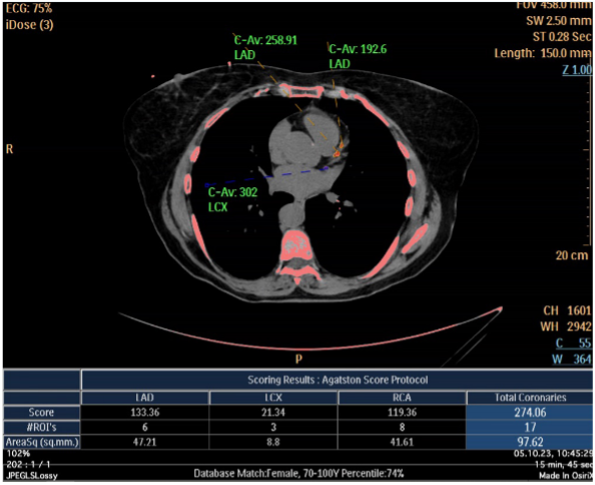

Accident cardiovasculaire

Examens d’imagerie médicale

Scanner score calcique ou score d’Agaston pour l’évaluation du risque cardiovasculaire. Au besoin, coronaires en scanner ou encore IRM cardiaque pour une étude plus approfondie en cas de symptômes.